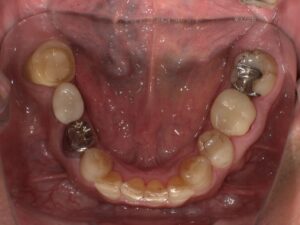

術前・術後写真

【術後】

最終的な被せ物(セラミッククラウン)の型行い取りを行い、いよいよ完成したセラミックの被せ物が入りました。

インプラント部分は本物の歯のように自然でしっかりと噛めるようになりました。

右下7番の状態が悪い患者さんでした。骨吸収を起こしており動揺もでていたので、抜歯も考えましたが、インプラントを選択されたので、骨吸収像は見られますが、動揺はほぼ無くなり噛めている状態を維持されています。インプラントは他の歯を守ることができる治療法だと思えた症例となりました。